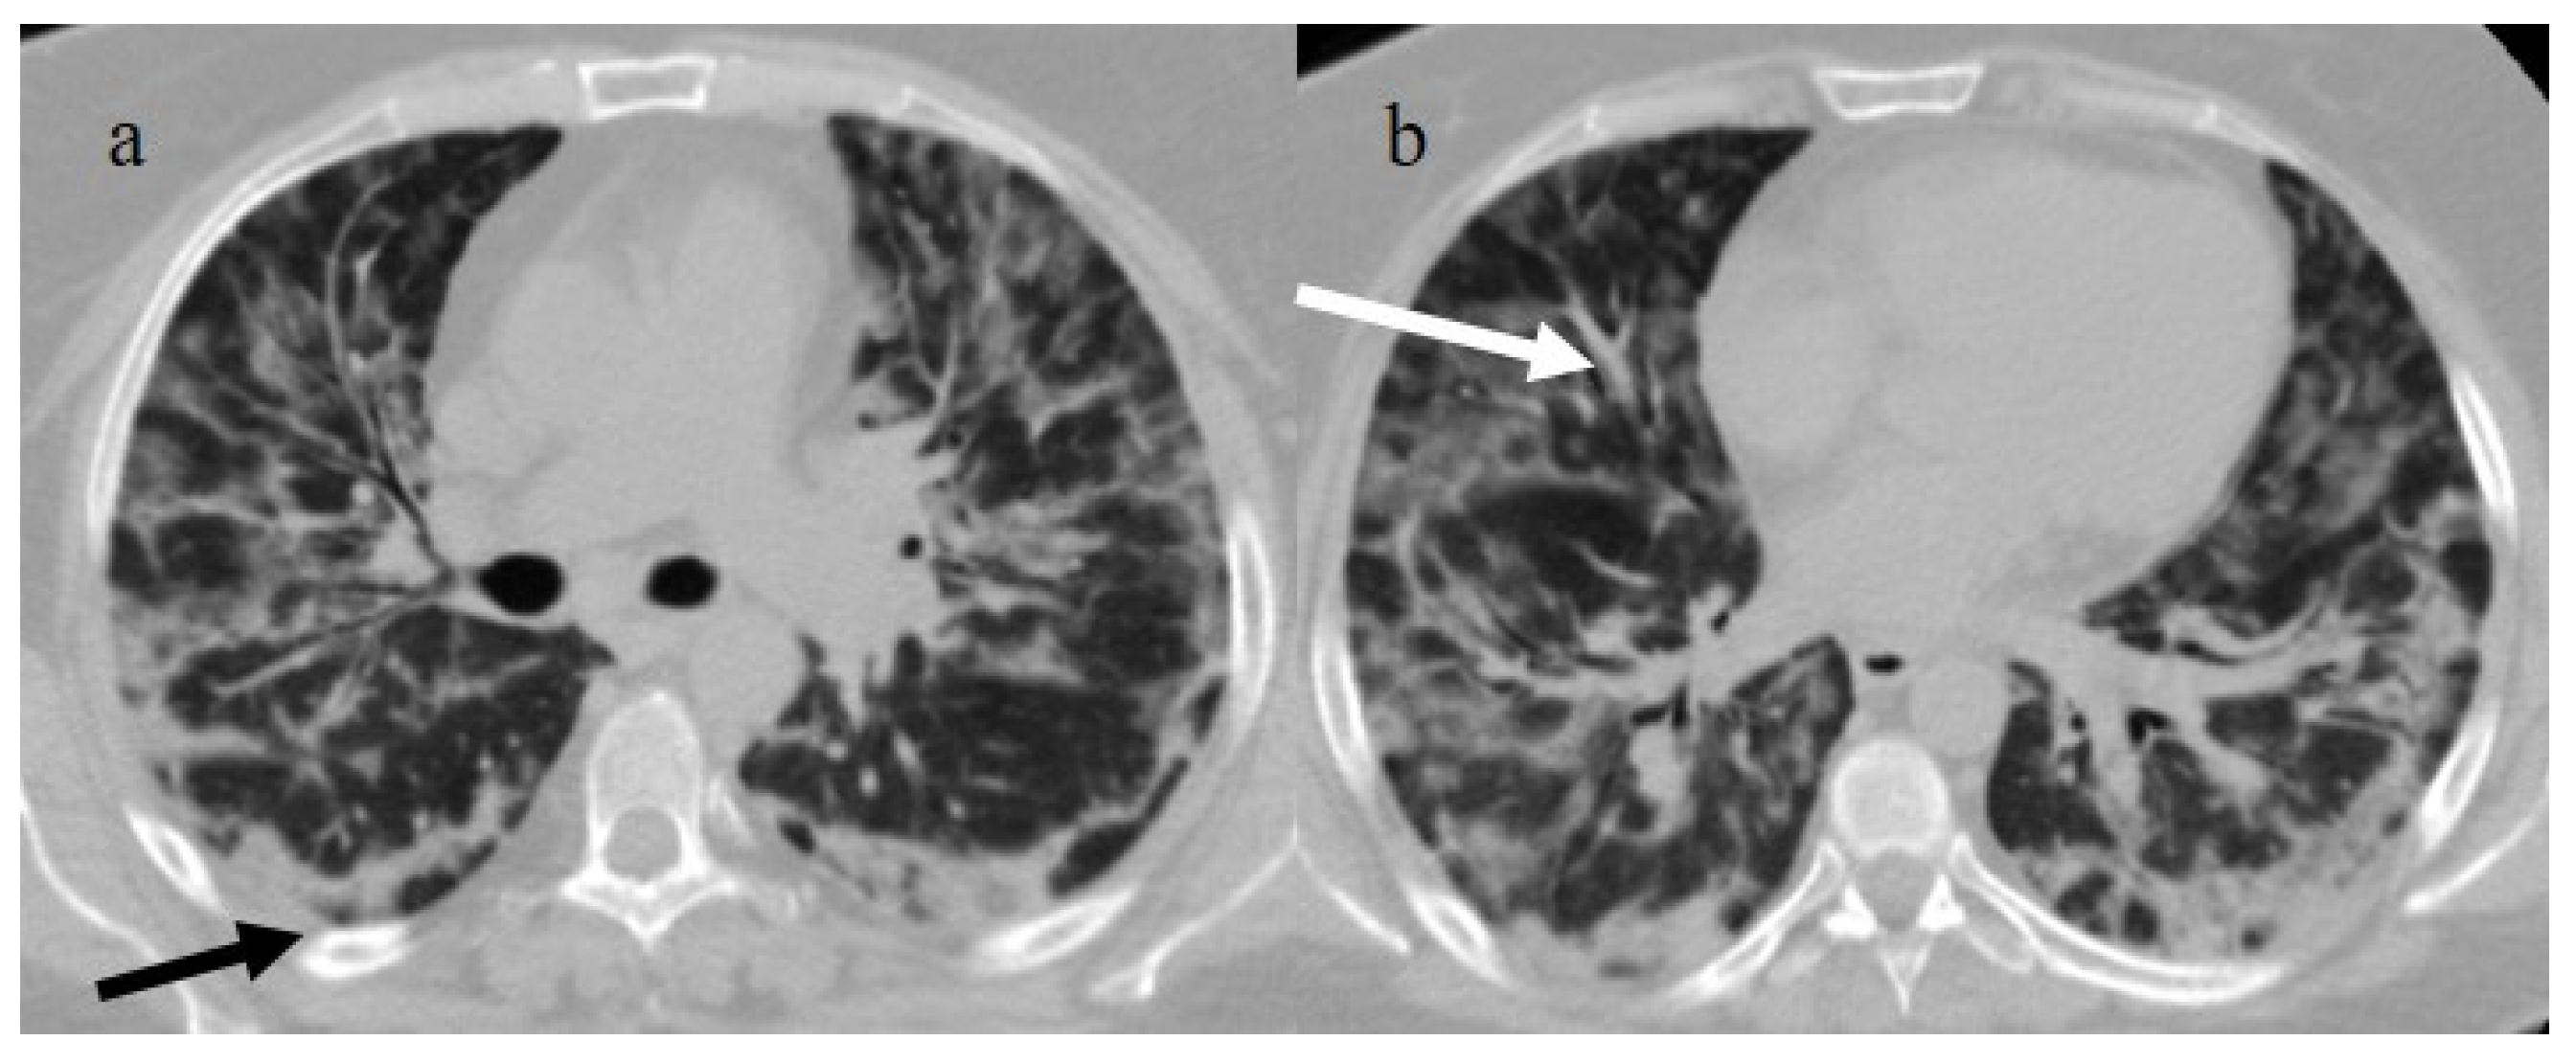

| Typical Appearance | GGOs with a crazy-paving pattern and consolidations in a peripheral and posterior or central-peripheral distribution; multilobar involvement; vascular enlargement, the halo and reversed halo sign; subpleural and parenchymal bands; and architectural distortion. They were predominant since the Delta wave. |

| Indeterminate Appearance | GGOs and consolidations with a unilateral, central, or upper-lobe distribution. |

| Atypical Appearance | Lobar consolidation, lung nodules or masses, miliary patterns, tree-in-bud patterns, cavitation, pleural effusion, central distribution, and lymphadenopathy. Atypical appearances were predominant during the Omicron waves. |

| Indeterminate appearance | Omicron variant | Ito et al., 2022 [54] | Cluster-like GGOs in the Omicron wave. |

| Atypical appearance | Omicron Variant | Hang et al., 2023 [75] | Patients infected with the Omicron variant presented a significantly higher prevalence of nodules, tree-in-bud patterns, and halo signs than patients with the original strain. |

| Ito et al., 2022 [54] | Prevalence of non-peripheral distribution with random distribution during the Omicron wave. | ||

| Lee et al., 2023 [28] | Peribroncovascular pneumonia with the Omicron variant and lower rates of severe pneumonia than the Delta variant. | ||

| Tsakok et al., 2023 [77] | Patients with an Omicron infection presented a greater frequency of bronchial wall thickening but less severe disease compared with the Delta variant. | ||

| Yang et al., 2022 [78] | Only 1.3% of patients infected with the Omicron variant had foci of pneumonia, and the GGOs were unilateral and centrilobular. | ||

| Yoon et al., 2023 [69] | Peribroncovascular GGOs or centrolobular foci during the Omicron wave with less extensive pneumonia. |